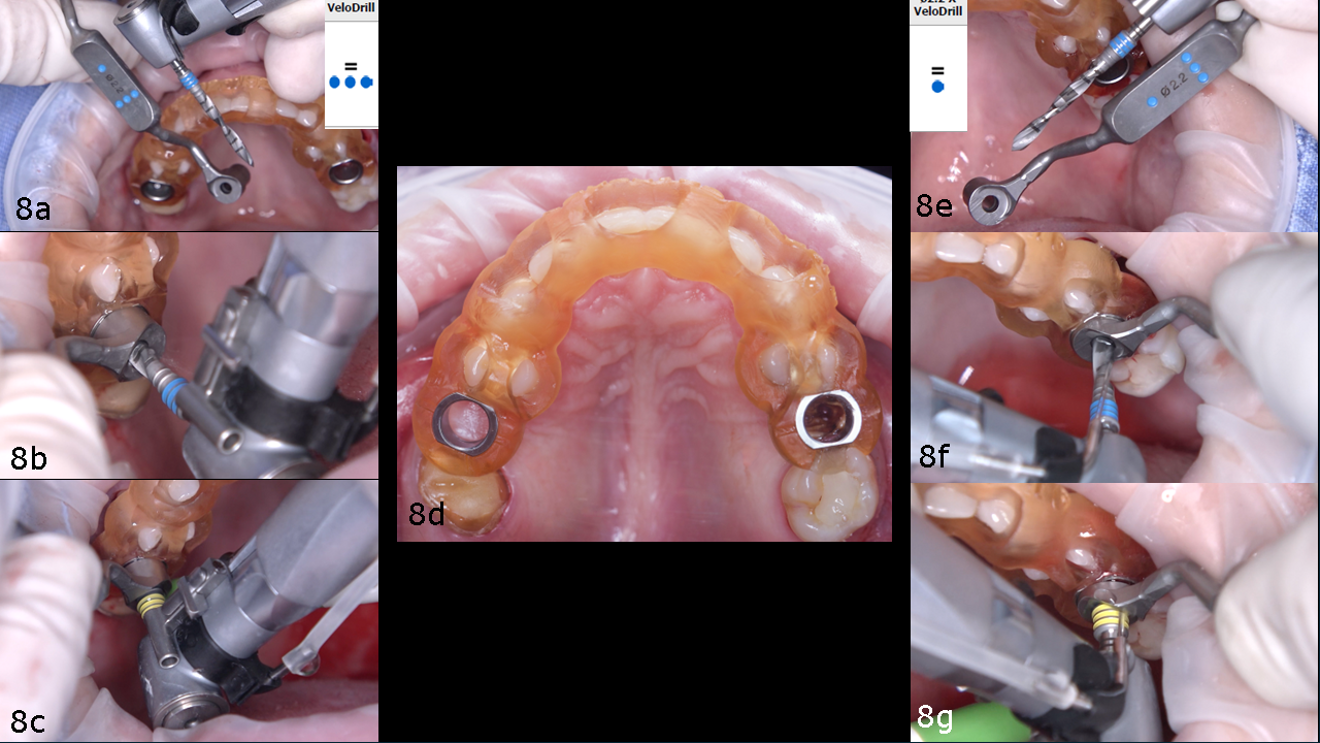

The surgical guide was inserted and verified for accurate fit. Osteotomy preparation was carried out according to the protocol generated by coDiagnostiX (Dental Wings), tailored to the planned implant types on each side (Figs. 8a–g). The Straumann BLX implant was placed into site #15, achieving primary stability at 30 N cm. The Straumann BLC implant was inserted into site #25, reaching primary stability at 50 N cm (Figs. 9a–g).